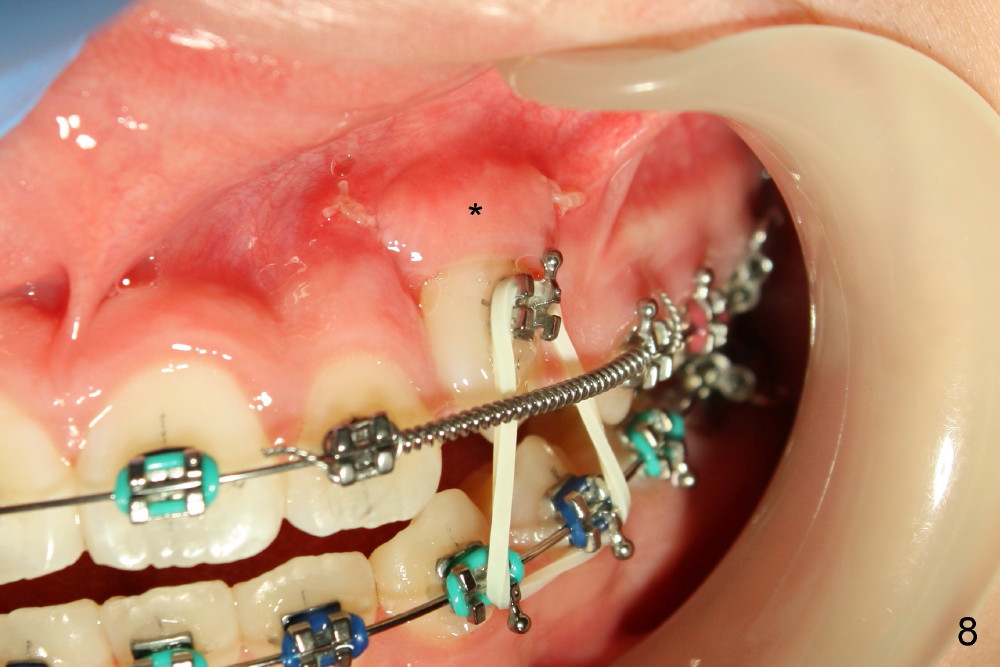

Eight days postop, the apical repositioning flaps have healed (Fig.7,8 *). The patient feels that U3s have been erupting more.

Two months postop, the canines have erupted substantially (Fig. 9 (downward arrow), 10, as compared to Fig.7,8). Since the long axis of the canines is oblique, the patient is instructed to wear elastic downward and backward (Fig.10 oblique arrow).